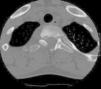

El osteoma osteoide es un tumor óseo benigno de tipo osteoblástico, que representa el 11% de los tumores óseos benignos. Su localización más frecuente es la diáfisis de huesos largos (fémur y tibia), aunque puede afectar otras localizaciones como la columna vertebral. Afecta con más frecuencia a los varones y en edades comprendidas entre los 7-25 años. Clínicamente se caracteriza por dolor continuo de predominio nocturno que suele remitir con AAS. Debe hacerse el diagnóstico diferencial con el osteoblastoma, metástasis y osteomielitis entre otros. El diagnóstico se realiza mediante pruebas de imagen TC (de elección), RNM o gammagrafía. El tratamiento de elección es la resección quirúrgica, aunque en ocasiones se puede realizar la electrocoagulación percutánea con radiofrecuencia.

Osteoid osteoma is an osteoblastic type of benign bone tumor that represents 11% of benign bone neoplasms. It is most frequently found in the diaphysis of the long bones (the femur and tibia), although other areas can be affected, such as the spine. It is most frequently found in male patients aged between 7 and 25 years. This entity is clinically characterized by continuous pain, mainly at night, which can be lessened by the use of acetylsalicylic acid. A differential diagnosis should be made with osteoblastoma, metastasis and osteomyelitis, among other entities. The diagnostic test of choice is computed tomography, while magnetic resonance imaging and scintigraphy are also useful. The treatment of choice is surgical resection, although percutaneous electrocoagulation with radio frequency can sometimes be performed.